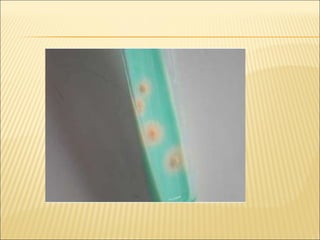

A ) Solid media 1-  Löwenstein-Jensen  (egg and also contain high concentrations of malachite green to overcome contamination with other bacteria) 2-   Middlebrook  7H10 and 7H11 are ( agar-based media.) Middlebrook media have been shown to achieve slightly higher isolation yields than egg-based media, but are considerably more expensive. B ) liquide media 1-  The BACTEC TB-460 2- MGIT960 systems All cultures reported positive for mycobacteria should be identified to the level of species using either biochemical or molecular methods Reading of results  1- Egg-based media they produce characteristic non-pigmented colonies, with a general rough and dry appearance simulating breadcrumbs 2- On agar based media, the colonies appear flat, dry and rough with irregular  edge .